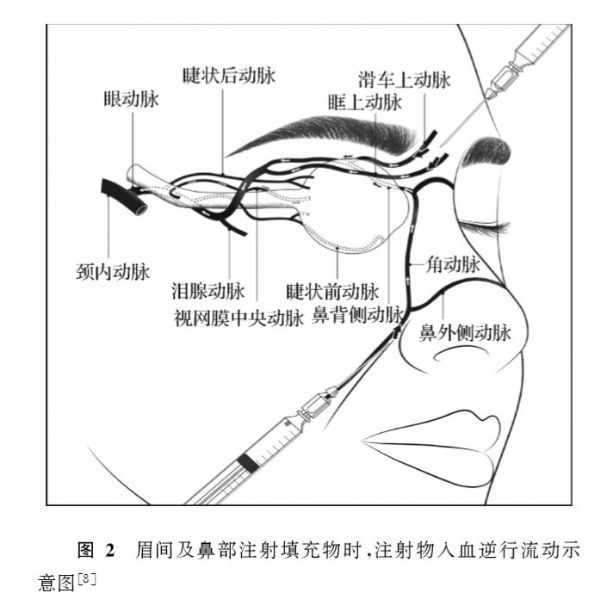

经滑车上动脉逆行或颈外动脉顺行介入溶栓治疗视网膜中央动脉阻塞伴同

发病机制眼动脉的分支有睫状前动脉,睫状后动脉,泪腺动脉,滑车上动脉

图l面部血管示意4.防治策略目前对于失明病例尚无成熟的治疗方法.

经滑车上动脉逆行或颈外动脉顺行介入溶栓治疗视网膜中央动脉阻塞伴同

【惟视诊室】面部注射玻尿酸,1小时后失明!

同时,鼻部的血液供应非常丰富,鼻子的血管贯穿面部构成了复杂而广泛的